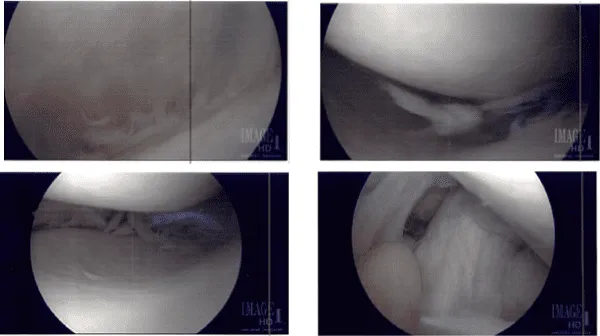

El torniquete estaba inflado. Se hizo un portal de entrada lateral y se accedió al telescopio. Se detectó daño osteocondral de OA grado 3 a grado 4 en la rótula inferior lateral. Se encontraron muchos restos en la rodilla, como en la bolsa suprapatelariana y la canaleta medial.

El endoscopio de la rodilla se trasladó al compartimento medial, donde se podían ver muchos restos y desgarros del menisco medial. Se hizo un portal de entrada medial. Se introdujo una sonda y se examinaron desgarros meniscales y se hicieron fotos. fue llevado.

Se insertó una afeitadora para limpiar los restos y los márgenes del menisco medial. Se realizó el ajuste final del menisco medial. La lesión también fue desbridada. La microfractura del defecto osteocondral rotuliano se realizó mediante punzones en coleta y se pudieron observar glóbulos de grasa subcondrales desde el lugar de la microfractura.

Imágenes intraoperatorias desde el inicio hasta el proceso final